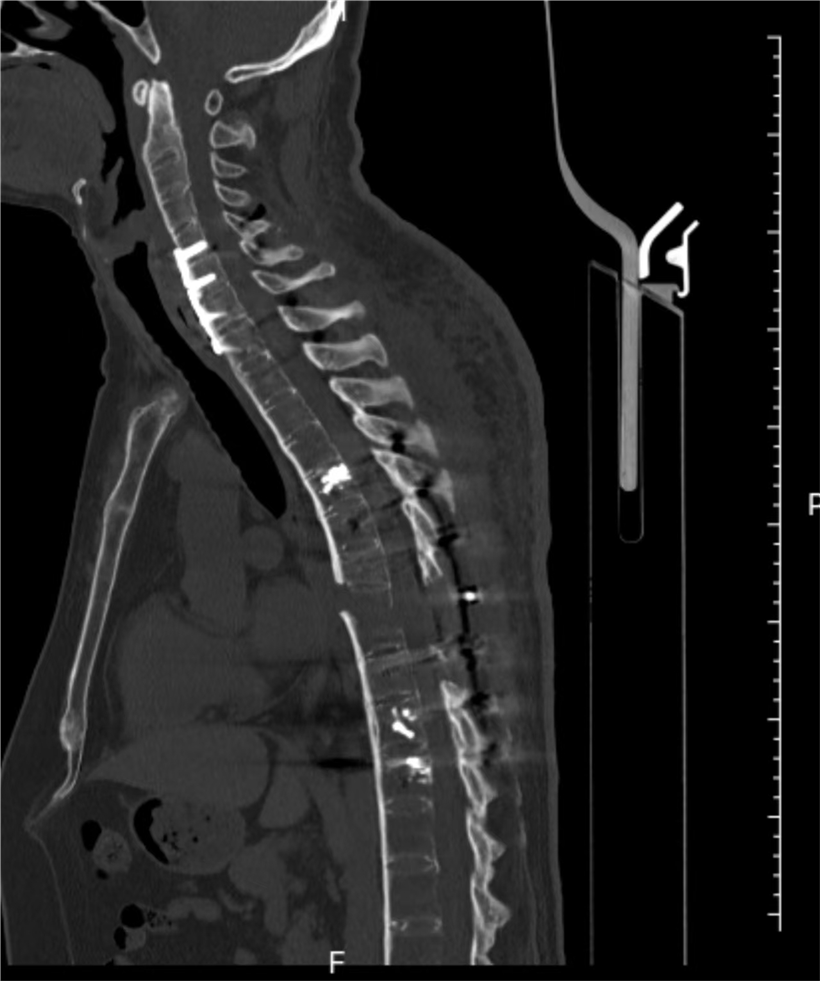

该患者因车祸导致颈椎横贯性损伤,颈椎前方极度不稳定,同时合并胸椎完全性骨折脱位,椎体漂浮、脊柱连续性中断。患者还有着多年的强直性脊柱炎病史,脊柱强直、骨质脆性高、稳定性极差,所幸入院时暂无明显神经压迫症状,四肢活动基本正常。然而,颈胸段脊柱序列已严重紊乱,麻醉后肌肉松弛,翻身等体位变化时稍有不慎,便可能引发脊髓严重受压,导致瘫痪甚至呼吸循环衰竭,手术难度与风险堪称脊柱外科手术的“珠穆朗玛峰”。

手术当日,多学科团队严阵以待,分阶段有序推进。先行仰卧位颈椎闭合复位,再通过颈前5厘米微创切口完成颈椎前路内固定,显著改善颈椎前方极度不稳定状况,重建颈椎前柱稳定性。随后,在神经电生理全程监测下,多学科协同完成Jackson床180°平稳翻转,成功破解术中核心高危难点。最后,经后正中入路开展颈椎后路固定,并对胸椎骨折完全脱位部位进行减压、精准复位与牢固内固定,彻底重建颈椎及胸椎脊柱正常序列。

经过13个小时的手术,患者的颈椎及胸椎脊柱序列得以重建。